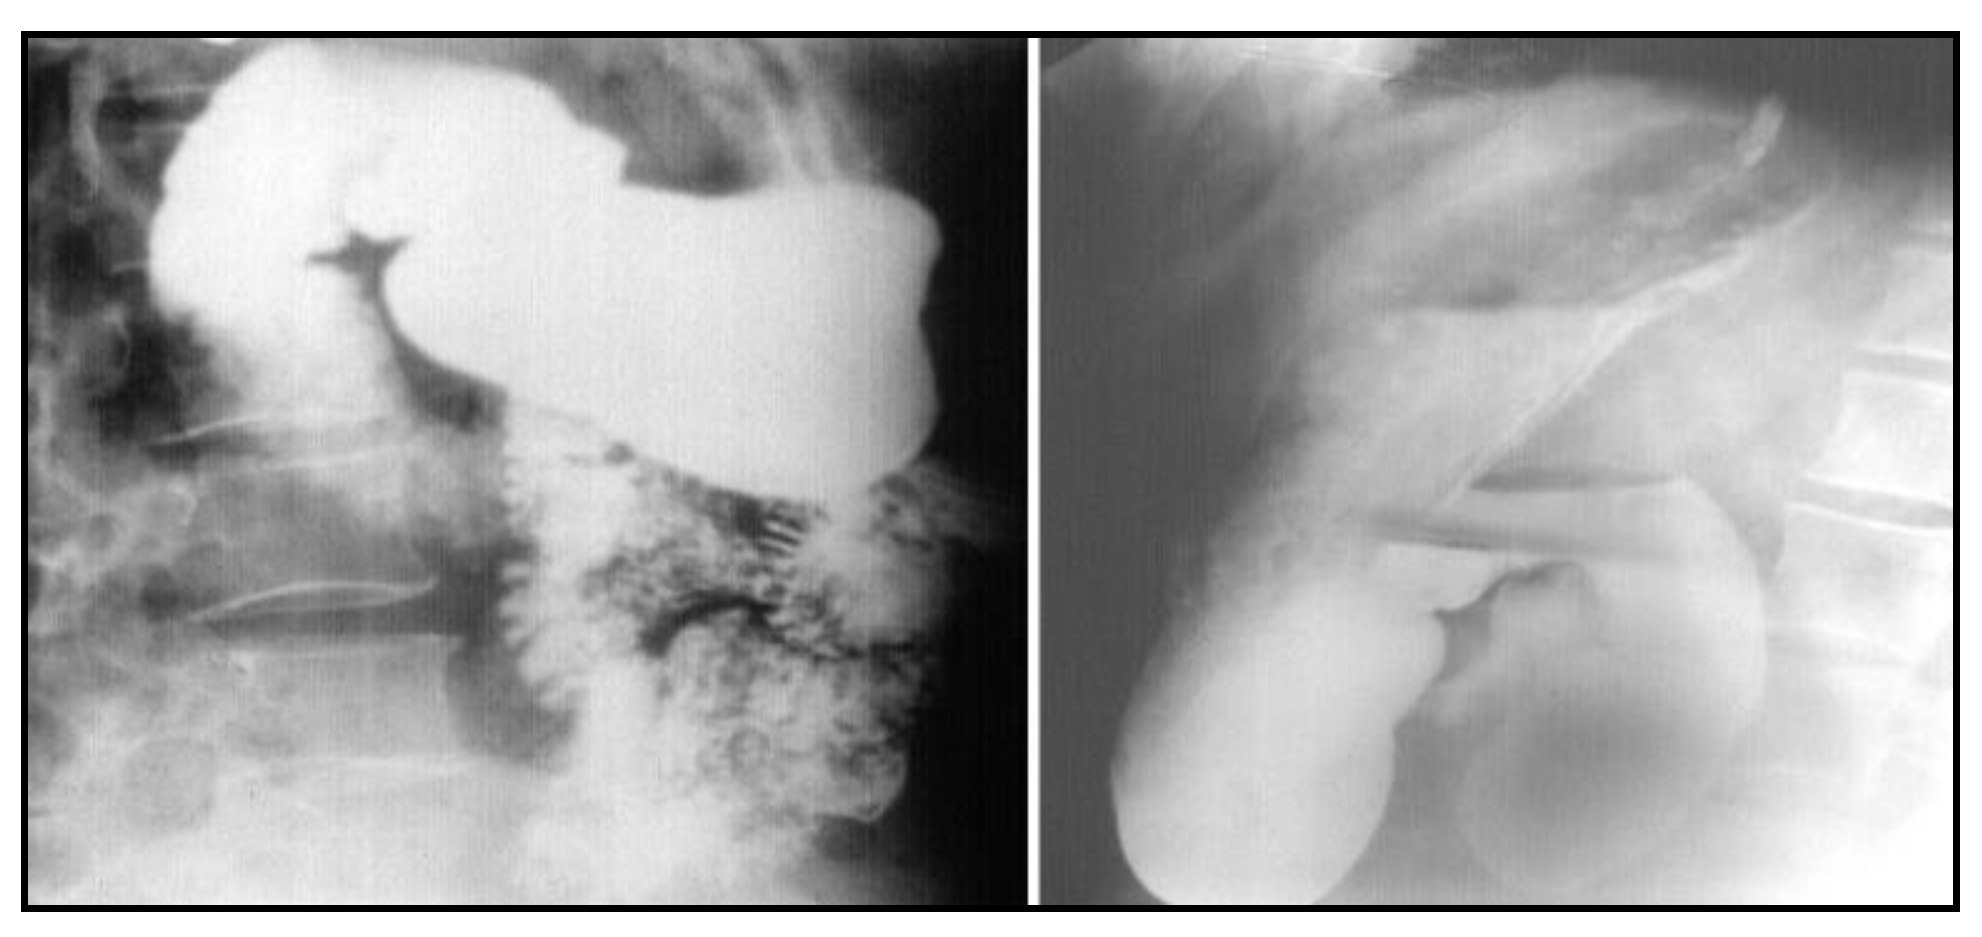

After nasogastric tube positioning, the upper endoscopy revealed dilated hypotonic stomach and duodenum with lesions of erosive gastritis and duodenitis. Using barium study of the upper gastrointestinal tract, we found a filling defect of the fourth portion of the duodenum, with dilated stomach and duodenum proximal to the site of obstruction; we also found gastroesophageal reflux without radiological signs of hiatal hernia (Figure 1). Ultrasonography and CT scan showed no metastases.

Figure 1.

Barium study of the upper gastrointestinal tract filling defect of the fourth portion of the duodenum with dilated stomach and duodenum proximal to the site of obstruction and gastroesophageal reflux without radiological signs of hiatal hernia.